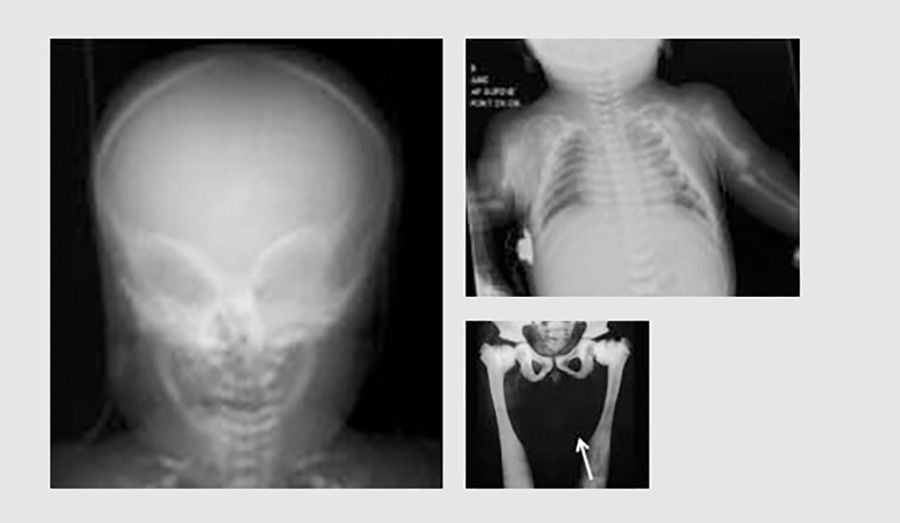

How is severe malignant osteopetrosis (SMO) diagnosed?

Severe malignant osteopetrosis (SMO) is often found in babies. It is usually diagnosed within the first year of life, often within the first 3 months. The first signs of the disease noticed by parents usually are:

• Vision problems

• Slow growth

• Failure to thrive

Other early signs are:

• Infections that happen over and over

• Repeated bone fractures

• Stuffy nose

• Unusual facial features

To find out if a child has SMO, the doctor may order an x-ray. Doctors look at the x-ray images to find the abnormal bone development that SMO causes. The x-ray and the patient’s physical symptoms usually lead to a diagnosis. This diagnosis can be confirmed through genetic testing.